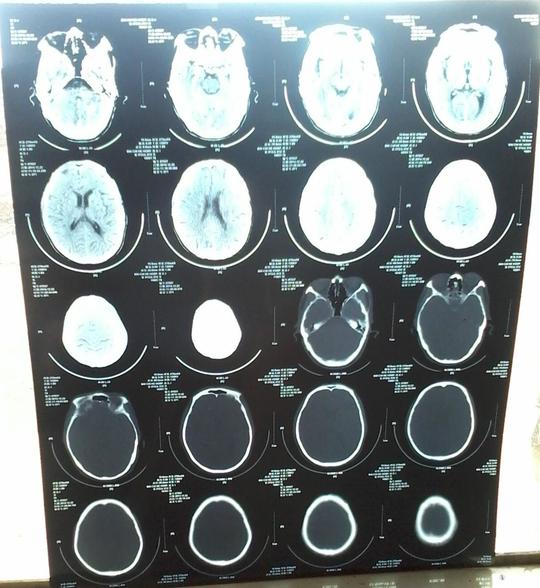

脑淤血导致肺部感染导致除了采取物理降温和挂消炎药

反复头晕除了脑供血不足,还可能是这6类病

首页>知识园地>心脑血管科>正文脑供血不足是指人脑某一局部

调节颅内压3.参与脑和脊髓的代谢4.维持正常ph